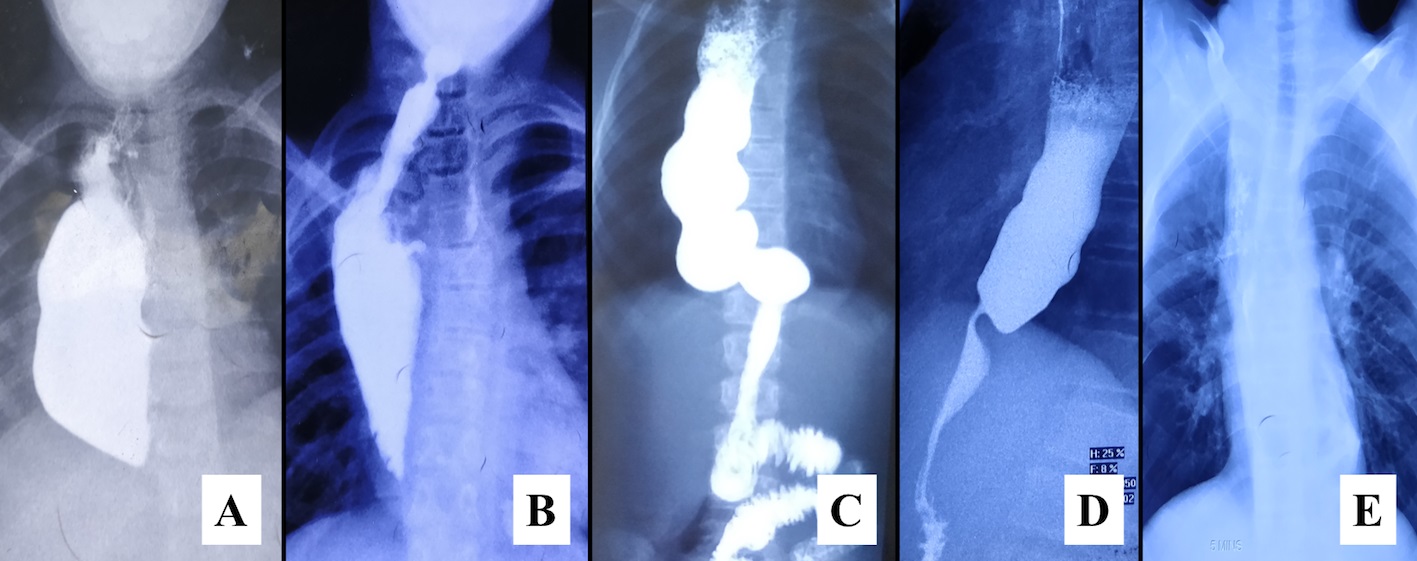

Figure 2

Oral contrast study (done during the study period) showing a healthy conduit in all the child.(A) Mild hold-up of contrast in pulled up stomach of 12-year child.(B) A normal calibre anastomosis between cervical esophagus and pulled up stomach is located in lower neck of 16-year child with free passage of contrast across it.(C) The elongated transposed stomach in the thorax in 10-year old child with normal passage of contrast.(D) 19-year old child with slow transit of contrast, however with complete contrast clearance (E) from transposed stomach.

b) Oral contrast swallow study: Healthy conduit was noted in all. There was no stricture or narrowing in any child. However, two children showed hold-up of contrast in the intrathoracic stomach with complete delayed clearance from the transposed stomach. (Fig. 2)